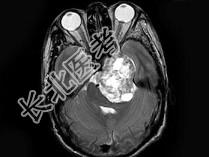

- 单项选择题男,38岁, 左侧面部麻木半年,头颅MRI见颅内占位性病变, 最可能的诊断为 ( )

B、三叉神经瘤